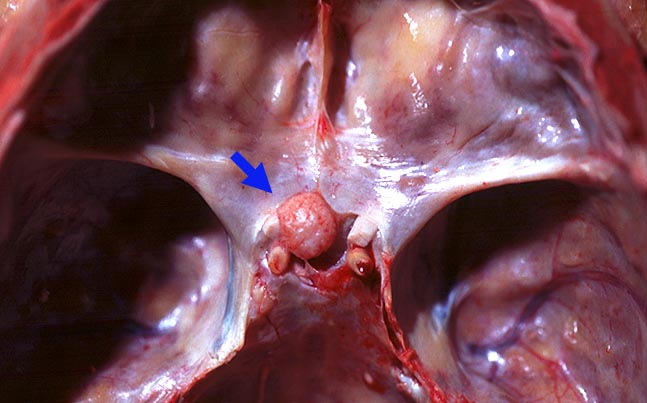

• Der Dura breitbasig aufsitzender scharf begrenzter halbkugeliger Tumor.

Die meisten Meningeome sind gutartig und fallen in die Kategorie WHO Grad I. Atypische Meningeome (WHO Grad II) machen zwischen 4.7-7.2% aller Fälle aus, anaplastische Menigeome (WHO Grad III) sind noch seltener. Meningeome sind oft multipel bei Patienten mit hereditärer Prädisposition und bei Neurofibromatose 2 sowie bei 10% der sporadischen Fälle. Meist wachsen Meningeome langsam. Sie sind in der Regel scharf begrenzt und sitzen der Dura breitbasig auf. Das Einwachsen von Meningeomgewebe in die Dura mater und/oder die benachbarte Schädelkalotte ist noch kein Malignitätszeichen und noch durchaus vereinbar mit einem benignen Meningeom WHO Grad I. Demgegenüber ist das Einwachsen in das benachbarte Hirnparenchym in aller Regel atypischen oder anaplastischen Meningeomen vorbehalten. Die Konsistenz ist prall-elastisch oder fest und das Tumorgewebe kann fokal verkalkt sein. Das Meningeom en plaque bedeckt flächenhaft die Dura als dünne Platte.